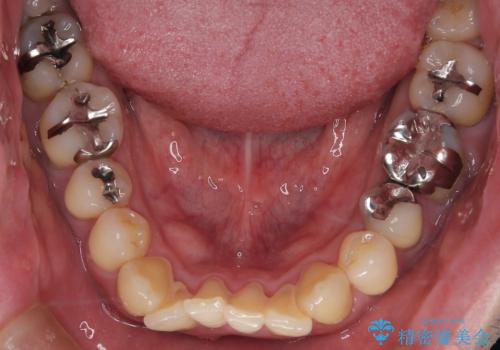

【メタル装置】1本のみ抜歯してワイヤー矯正

- 30代男性

- 矯正装置

- メタル装置

- 右上2番目の歯が舌側転位していることと前歯の叢生(がたつき)を主訴に来院されました。

下のがたつきをとるために、IPR(歯と歯の間を削る処置)も行って歯を並べていきます。